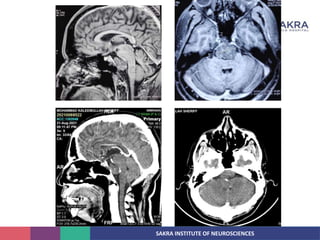

• NCCT:

• Relatively well circumscribed, moderately hyperdense midline or paramedian clival

mass with permative lytic bony changes.

• Intratumoral calcification generally represent sequestration from destroyed bone.